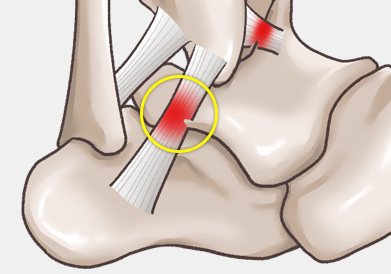

발목 인대 파열은 발목 관절을 지지하는 인대가 외부 충격이나 과도한 움직임으로 인해 늘어나거나 찢어지는 손상을 말합니다.

주로 다음 그림처럼 내반(inversion)에 의해 바깥쪽 인대가 파열되는 경우가 흔하며, 그 중에서도 전거비인대 및 종비인대의 손상 여부가 수술을 결정하는 데 가장 중요합니다.